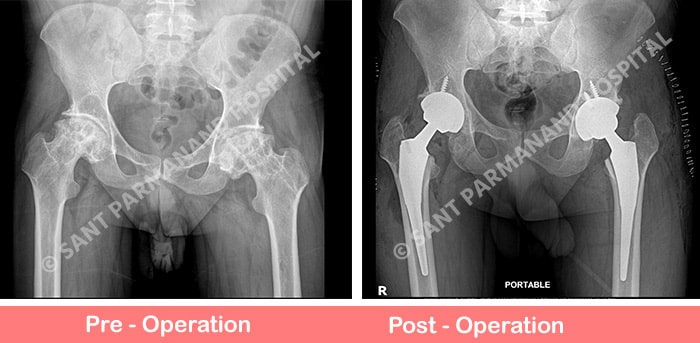

50 yrs old gentleman with no comorbidities, came with complaints of pain in both hip joints and was having difficulty in walking for the past 6 months. His X-Ray showed damaged hip joints with stage 4 AVN changes. Thus he planned for Hip Replacement Surgery for both hip joints in single sitting. Post operative xray showed uncemeted Total Hip Replacement (ceramic on poly) with no limb length discrepancy.

We routinely performed such surgeries on regular basis with great outcomes. Patient mobilized next day with support comfortably. These hip replacement surgeries require meticulous pre and intraoperative planning to prevent any limb length discrepancy.